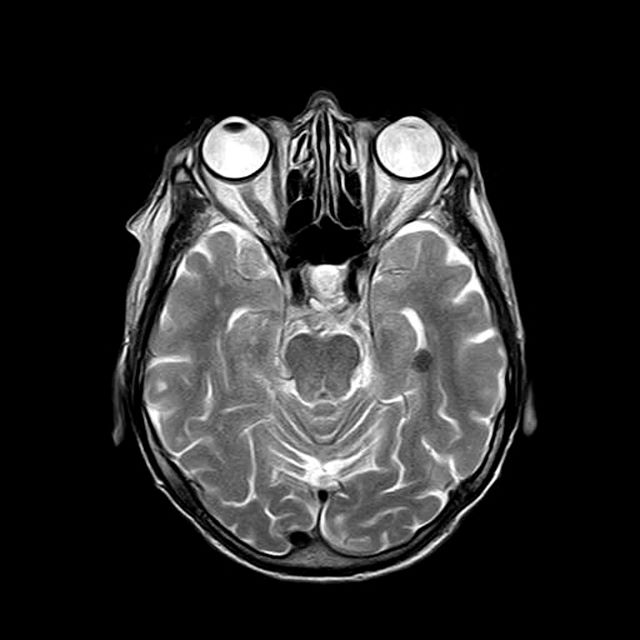

Men småningom var jag äntligen på plats och fick ta av mig allt utom trosor och strumpor, samt sätta på en urtvättad sjukhusskjorta. En vänlig sköterska hjälpte mig att få in öronproppar, ovanpå det stora hörlurar och så en ”burk” runt hela huvet. (Som på bilden, men jag var utan skägg och iklädd sjukhusskjorta).